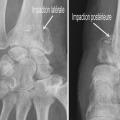

Au niveau métaphysaire le déplacement peut être postérieur ou antérieur (fig. 6). En ce qui concerne le déplacement postérieur, il est important de se souvenir que la surface articulaire regarde vers l’avant. En d’autres termes, dès que cela n’est plus le cas, même si la surface articulaire n’est pas orientée vers l’arrière, il s’agit d’un déplacement postérieur. Classiquement, le déplacement postérieur est lié à un mécanisme dit en compression-­extension, c’est-à-dire une chute sur la main, le poignet étant en extension (fig. 7). Le déplacement est dit antérieur s’il y a une exagération de l’orientation antérieure de l’épiphyse radiale. Ce déplacement est classiquement lié à un mécanisme dit en compression-flexion, c’est-à-dire une chute sur la main, le poignet étant en flexion (fig. 7). La plupart du temps, ce déplacement postérieur ou antérieur s’accompagne également d’un déplacement externe, avec un tassement au niveau de la corticale latérale (fig. 8). Outre le déplacement antérieur, postérieur ou latéral, il est très important d’analyser au niveau du foyer de fracture métaphysaire l’importance de la comminution qui peut être uniquement postérieure, ou antérieure, ou circonférentielle, ce qui conditionne la stabilité de la fracture et oriente vers le type d’ostéosynthèse à réaliser.

L’analyse de l’épiphyse va permettre de déterminer si la fracture est articulaire ou extra-articulaire. Dans la très grande majorité des cas, la fracture est articulaire. Il existe très fréquemment un fragment postéromédial qu’il est important de rechercher car il faudra le stabiliser lors du traitement. Mais la fracture articulaire peut être plus complexe, en T ou en croix (fig. 9). Enfin, il peut exister des enfoncements de fragments ostéochondraux à l’intérieur du spongieux épiphysaire (appelé par les Anglo-Saxons « die punch »). Sur les fragments épiphysaires s’attachent les ligaments radiocarpiens. Ainsi, une traction dans l’axe permet, par le biais de ses ligaments (effet de ligamentotaxis), de réduire au moins partiellement la fracture. En revanche, les fragments ostéochondraux qui sont enfoncés dans le spongieux n’ont pas d’attaches ligamentaires et ne se réduisent pas par les manœuvres de traction. Il peut arriver que les fractures soient uniquement épiphysaires. C’est le cas des fractures dites marginale antérieure, marginale postérieure et cunéenne externe. Cette dernière est importante à connaître et à dépister car elle s’accompagne relativement fréquemment de lésion ligamentaire intracarpienne, notamment scapholunaire.